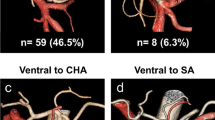

As shown in Table 1, the RGA was identified in 77 cases (77.0 %). As earlier studies had neglected hepatic arterial anomalies in the analysis of RGA ramification points [11, 16], we precisely examined RGA ramification according to hepatic arterial running patterns. First, branching patterns of the hepatic artery were classified into four types: RHA + LHA type, both being derived from the proper hepatic artery (PHA) (Fig. 2a, n = 82); the replaced RHA + LHA type, with the replaced RHA coming from the SMA or celiac artery and the LHA from the CHA (Fig. 2b, n = 10); the RHA + replaced LHA type, where the RHA comes from the CHA and the replaced LHA from the LGA (Fig. 2c, n = 5); the replaced RHA + replaced LHA type, where the replaced RHA comes from the SMA and the replaced LHA from the LGA (Fig. 2d, n = 3). In the replaced RHA + replaced LHA type, the gastroduodenal artery (GDA) directly branches from the so-called CHA. The root of the GDA was defined as the “branching point (BP).” The RGA ramification patterns were then classified into three types: the distal type, in which the RGA ramifies from the distal arteries (PHA, RHA, and LHA) relative to the BP; the proximal type, in which the RGA ramifies from the CHA or BP; and the caudal type, in which the RGA ramifies from the GDA (Figs. 2, 3). In the replaced RHA + replaced LHA type, the rightward turning point (so-called CHA) to the point of descent (so-called GDA) was defined as the BP (Fig. 2d). According to these definitions, 53 RGAs (68.8 %) were classified into the distal type (Fig. 3a), 11 (14.3 %) into the proximal type (Fig. 3b), and 13 (16.9 %) into the caudal type (Fig. 3c). The relationships between hepatic artery ramification type and RGA ramification type are shown in Table 1.

Various patterns of hepatic arteries on 3D angiography. The branching point of the GDA is named the “branching point (BP)” (arrowhead). a RHA + LHA type: both the RHA and LHA are from the proper hepatic artery (PHA). b Replaced RHA + LHA type: the replaced RHA is from the SMA (gray arrow) and the LHA is from the CHA. c RHA + replaced LHA type: the RHA is from the CHA, and the replaced LHA is from the LGA (white arrow). d Replaced RHA + replaced LHA type: the replaced RHA is from the SMA (gray arrow), and the replaced LHA is from the LGA (white arrow). In the last case, the GDA directly branches from the so-called CHA

Right gastric artery (RGA) ramification patterns. a Distal type (n = 45) in which the RGA ramifies from distal arteries relative to the BP. b Proximal type (n = 6) in which the RGA ramifies from the CHA or the BP. c Caudal type (n = 12) in which the RGA ramifies from the gastroduodenal artery (GDA). Arrows indicate the RGA